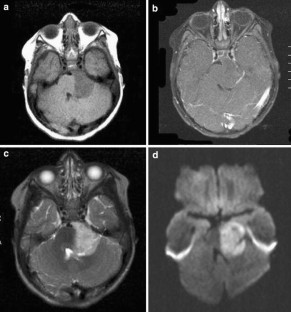

Fig. 1